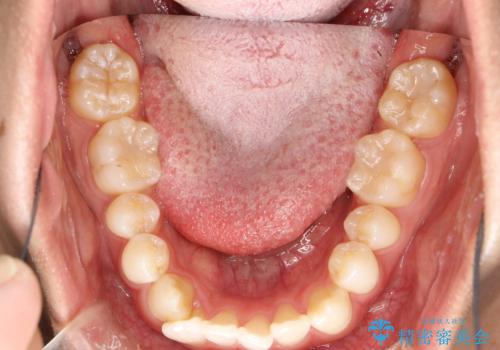

インビザラインによる矯正治療(非抜歯) 下の前歯の歯並びの改善

- 主に下の歯並びの改善を主訴としてご来院されました。

右下の犬歯と前歯が大幅に重なっているのと、歯の向きも大きく横に倒れています。この部位の正常な配列のためには、3次元的に大幅な移動が必要となりました。

インビザラインの特色を生かした歯牙移動計画を作成し、非抜歯にて治療を行いました。